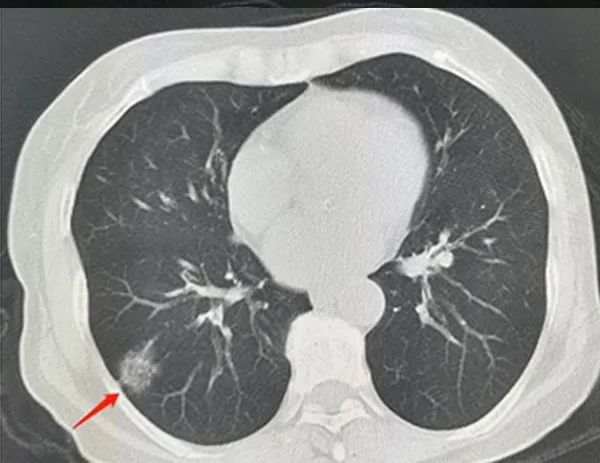

亚实性结节

亚实性肺结节:所有含磨玻璃密度的肺结节均称为亚实性肺结节,其中磨玻璃病变指CT显示边界清楚或不清楚的肺密度增高影,但病变密度不足以掩盖其中走行的血管和支气管影。

亚实性肺结节中包括纯磨玻璃结节、磨玻璃密度和实性密度均有的混杂性结节,后者也称部分实性结节。